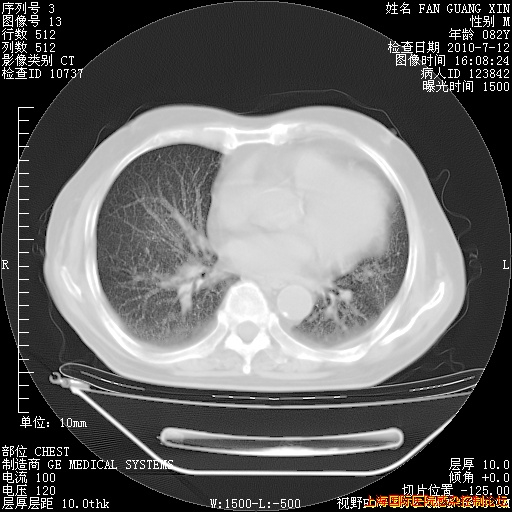

今天复查CT

今天CT

整整相隔30天的肺部CT好像有所好转啊。甲强龙减量第3天,需要观察体温。